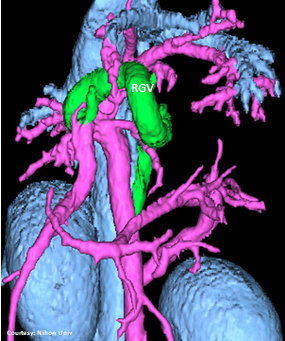

“LGC +PancV -GSV” Left Gastro-Caval Shunt with Pancreatic Vein contribution and absent Gastro-splenic vein (GSV does not enter PV)

Courtesy: Nihon Univ

WEISSE 2022

slide20